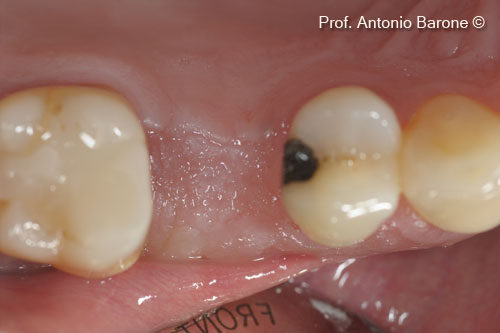

Hình ảnh lâm sàn mặt nhai sau khi bộc lộ implant

Trụ cấy ghép